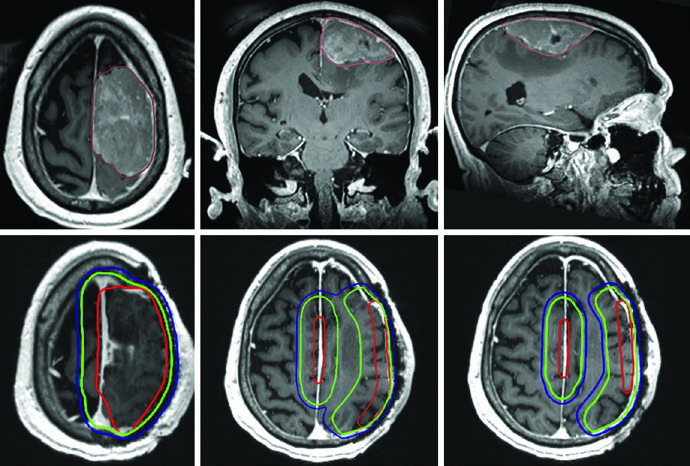

O ponto central é este: a delineação precisa tanto dos volumes-alvo quanto dos órgãos de risco determina qual técnica será mais vantajosa para cada paciente. E para isso, a corregistração de RM diagnóstica no CT de planejamento não é opcional — é fortemente recomendada. As sequências T1 pós-contraste e FLAIR permitem visualizar tanto o tumor residual quanto o edema perilesional, enquanto sequências T1 simples e 3D-T2/CISS ajudam a delinear estruturas como hipocampo e nervos cranianos. Para mais contexto sobre os princípios gerais de delineamento, confira nosso guia completo sobre delineamento de volume alvo na radioterapia.

Alguns erros recorrentes no planejamento de tumores malignos do SNC merecem destaque. O mais comum é aplicar expansões isotrópicas sem respeitar as barreiras anatômicas. O CTV de um glioblastoma frontal não deve cruzar a linha média — a menos que o joelho do corpo caloso esteja em risco, caso em que essa estrutura deve ser explicitamente incluída. Outro erro é ignorar a diferença entre as sequências de RM: o GTV1 deve ser baseado no FLAIR (edema perilesional), enquanto o GTV2 usa a T1 pós-contraste (doença captante residual).